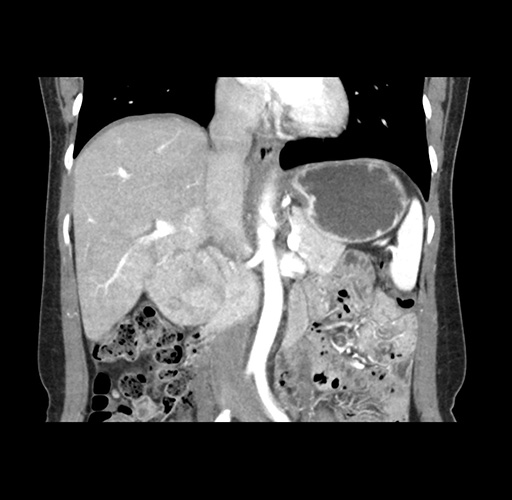

Imaging Analysis

Look through the patient's CT scan to identify any areas of concern for the necessary procedure.

Based on your CT findings, which issue(s) would give reason for "planned slowing down moment(s)" in this case?

Considering a standard left lateral sectionectomy procedure, what step(s) of the operation would you do differently in this case ?